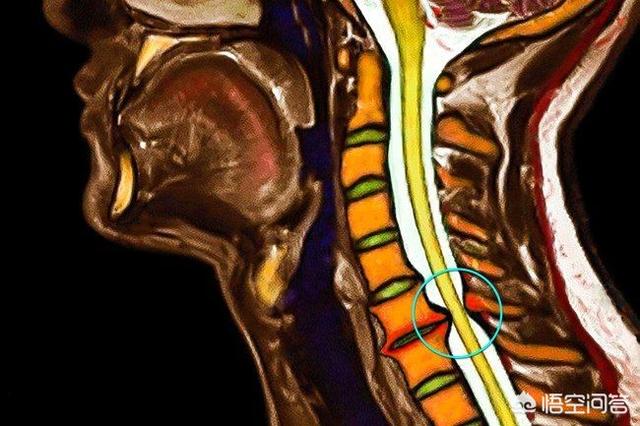

脊髓型颈椎病多数都是由于颈椎的椎间盘突出、椎体后缘的骨刺、韧带的骨化、黄韧带肥厚等原因严重的压迫了颈椎椎管内的脊髓而导致脊髓缺血出现的一些症状。很多患者如果确诊为脊髓型颈椎病会出现手笨拙无力、走不了直线、容易摔倒、出现痉挛步态的一些表现,有一些严重的患者甚至会出现排便困难。